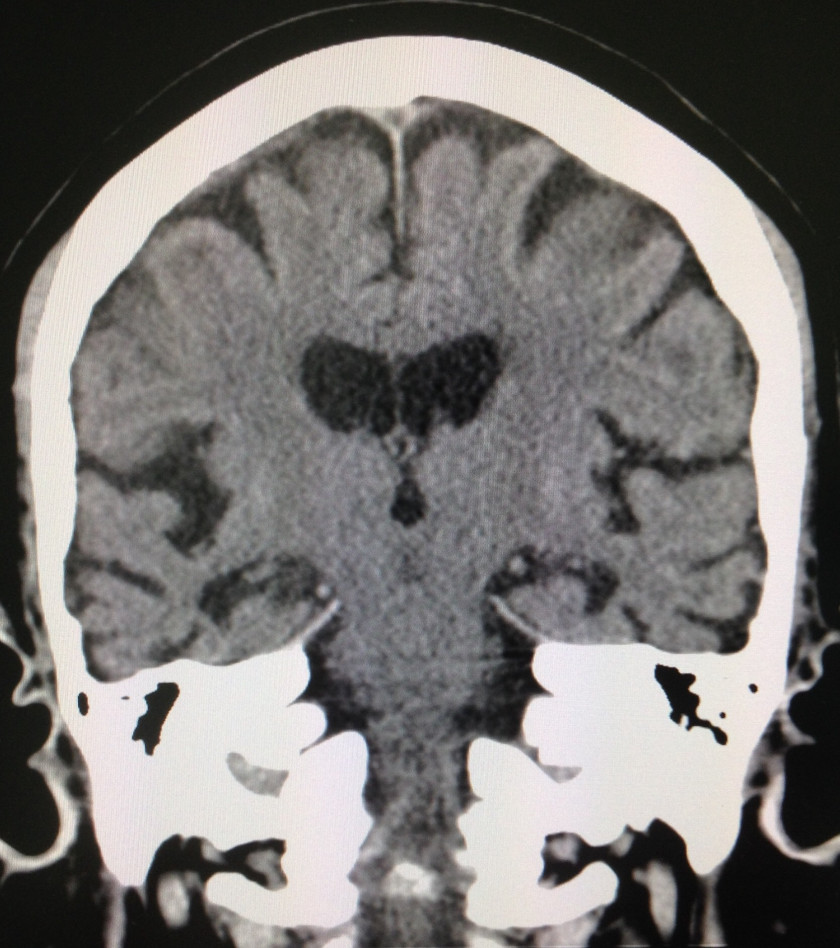

80代女性、妄想と記憶に問題があり受診。妄想の主体はモノ取られ妄想ですね。2年前から異常が認められるようになった。持参された頭部MRIの写真コレも2年前のもの。

まっ コレでヨシとしました。赤い⭕️で囲んだ部分はガラーンとしていますが・・・

例の“海馬”が存在する部位、改訂長谷川式10/30 遅延再生全滅。写真を出しませんでしたが、前頭葉の萎縮もある年齢です。

でも、それ以上に激しい萎縮が頭頂葉にありました。図形も時計も書けません。

この症例は画像でみたままの状況と言って良いと思います。重要なことは、萎縮=機能障害は常に成立しないのです‼️